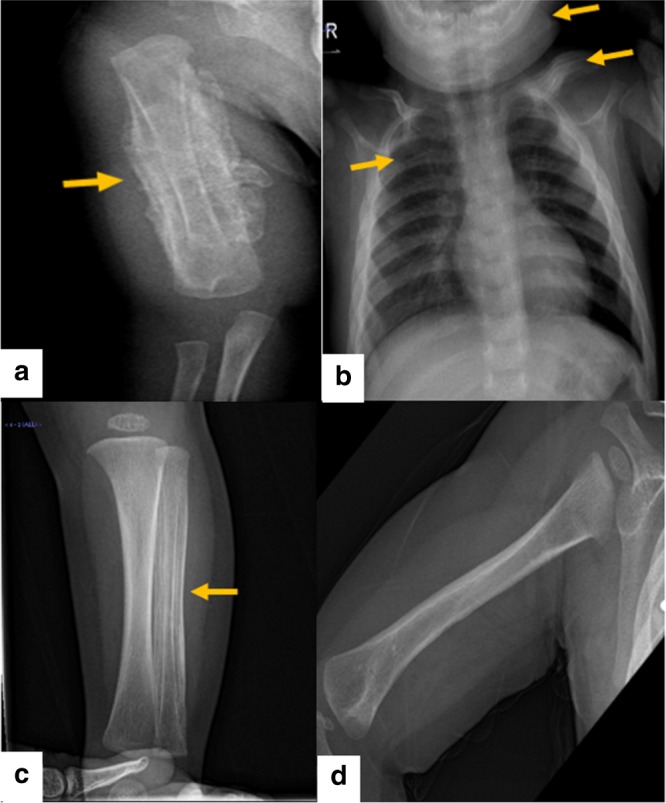

对右臂进行 X 光检查,显示沿右肱骨的整个骨干骨膜反应旺盛(图 1a)。 进一步评估包括 X 线骨骼检查,显示一侧肩胛骨、一根腓骨、下颌骨和许多肋骨有明显的骨膜反应(图 1b)。 根据临床和放射学检查结果,诊断为 ICH。 尽管德托尼-卡菲病可能具有短暂性,但开始使用吲哚美辛(每天 5mg/kg)治疗,并且病变在几个月内完全消失,正如后续放射学检查所证明的那样(图 1c)。 经过 1 年的随访,患者完全康复,没有骨骼畸形和/或升高的炎症标志物。 他仍在服用低剂量的消炎痛(每天 1mg/kg)。

患者的射线照相检查。 a 沿右肱骨整个轴的骨膜反应。 b 沿左锁骨、肋骨和下颌骨的骨膜反应。 c 沿腓骨的骨膜反应。 d 肱骨骨膜完全消退